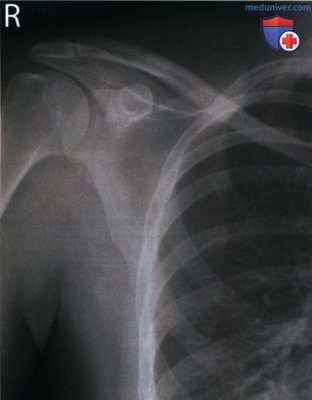

Рекомендации по анализу изображений (рис. 1 и 2):

РИСУНОК 1 Рентгенограмма акромиально-ключичного сустава в ПЗ проекции (без нагрузки): правильная укладка. РИСУНОК 2 Рентгенограмма акромиально-ключичного сустава в ПЗ проекции (с нагрузкой): правильна укладка.

• Латеральный отдел ключицы направлен горизонтально

• Между латеральным концом ключицы и верхушкой акромиального отростка визуализируется промежуток в 0,3 см (рис. 5)

• Наложение латерального конца ключицы на акромиальный отросток минимально

• Ключица и верхний угол лопатки находятся на одном поперечном уровне (рис. 6 и 7)

• АК сустав находится в центре экспозиционного поля как при рентгенографии без нагрузки, так и при рентгенографии с нагрузкой (рис. 8 и 9)

• В экспозиционное поле входят латеральный конец ключицы, акромиальный отросток и верхний угол лопатки

• Рентгенограмма с нагрузкой помечена словесным маркером или стрелкой, указывающей вниз

а) Показания к исследованию. Чтобы выявить повреждение АК связки, натянутой между латеральным концом ключицы и акромиальным отростком, сначала выполняют рентгенографию АК сустава в ПЗ проекции без нагрузки. Затем проводят рентгенографию в этой же проекции с нагрузкой, для чего пациент удерживает каждой рукой предметы массой 2-3,5 кг (см. рис. 3 и 4). При повреждении АК связки суставная щель АК сустава на рентгенограммах с нагрузкой будет шире, чем на рентгенограммах без нагрузки.